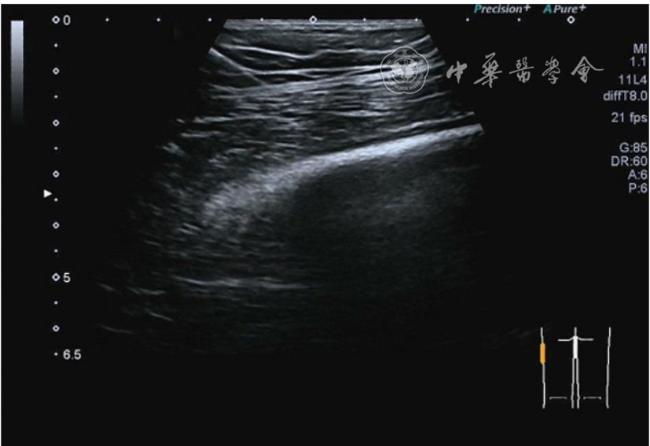

4.腓总神经分支卡压的治疗。常见腓浅神经、腓深神经感觉支卡压。主要表现为足背侧的感觉减退。腓深神经只支配第一、二足趾之间的感觉,腓浅神经支配的感觉区域较多,第一、二足趾之间外的足背感觉均由腓浅神经支配,根据感觉障碍区域确定卡压神经,超声可以明确卡压部位和原因。超声可显示卡压神经增粗,回声减低,局部软组织回声不均匀等(图4445)。治疗以液压松解药物注射为主。以腓深神经为例进行介绍。常见卡压部位在小腿和足背部。根据卡压部位不同,患者采取不同的体位。如果在小腿部采用平卧位,膝关节伸直位即可。穿刺区域常规消毒,探头涂抹耦合剂后套入无菌手套碘伏消毒或使用无菌耦合剂。将探头置于患者皮肤表面,小腿部位采用短轴扫查,确定神经卡压最明显的部位后,用一次性5 ml注射器,应用25G注射针头抽吸0.5%利多卡因4 ml+地塞米松3 mg平面内进针到达神经周围,注意回抽无血液回流后进行注射(图46),完成注射松解,拔出针头,局部压迫3分钟,创可贴覆盖。如果在足背部可以采取平卧位,屈髋、屈膝将足平放于治疗床面。治疗前准备同小腿部,采用长轴显示神经,确定神经卡压最明显的部位后,用一次性5 ml注射器,应用25G注射针头抽吸0.5%利多卡因2 ml+地塞米松1 mg平面内进针到达神经表面进行注射(图47),完成注射松解,拔出针头,局部压迫3分钟,创可贴覆盖。

图46 腓深神经在小腿近端腓深神经、腓浅神经分开处卡压及穿刺注射治疗超声图像